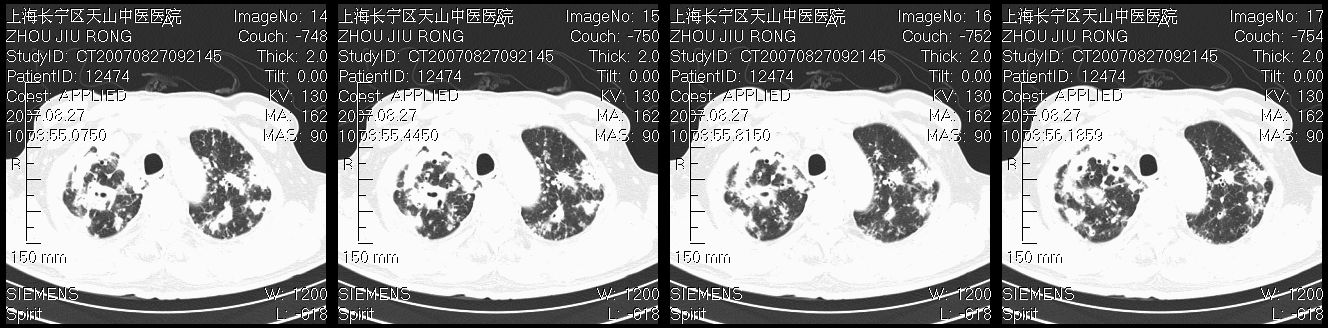

以下是引用zjzjr在2007-8-30 21:47:00的发言:[br]双肺弥漫性结节状、斑片状影,部分形成空洞,病灶以双肺上叶为著(符合结核发病部位),纵隔内见肿大淋巴结影。支持双肺继发性结核伴右上肺空洞形成。

以下是引用zjzjr在2007-8-30 21:47:00的发言:[br]双肺弥漫性结节状、斑片状影,部分形成空洞,病灶以双肺上叶为著(符合结核发病部位),纵隔内见肿大淋巴结影。支持双肺继发性结核伴右上肺空洞形成。

以下是引用gaoshengjiang在2007-8-31 10:24:00的发言:[br]双肺弥漫性斑片状影及多发空洞影,其间夹杂多量条索状影,胸膜肥厚、粘连并有结节状改变,纵隔多枚淋巴结肿大,考虑1双肺继发型肺结核合并感染?2韦格氏肉芽肿?[br] 支持!

以下是引用zjzjr在2007-8-30 21:47:00的发言:[br]双肺弥漫性结节状、斑片状影,部分形成空洞,病灶以双肺上叶为著(符合结核发病部位),纵隔内见肿大淋巴结影。支持双肺继发性结核伴右上肺空洞形成。

以下是引用zjzjr在2007-8-30 21:47:00的发言:[br]双肺弥漫性结节状、斑片状影,部分形成空洞,病灶以双肺上叶为著(符合结核发病部位),纵隔内见肿大淋巴结影。支持双肺继发性结核伴右上肺空洞形成。

以下是引用zjzjr在2007-8-30 21:47:00的发言:[br]双肺弥漫性结节状、斑片状影,部分形成空洞,病灶以双肺上叶为著(符合结核发病部位),纵隔内见肿大淋巴结影。支持双肺继发性结核伴右上肺空洞形成。